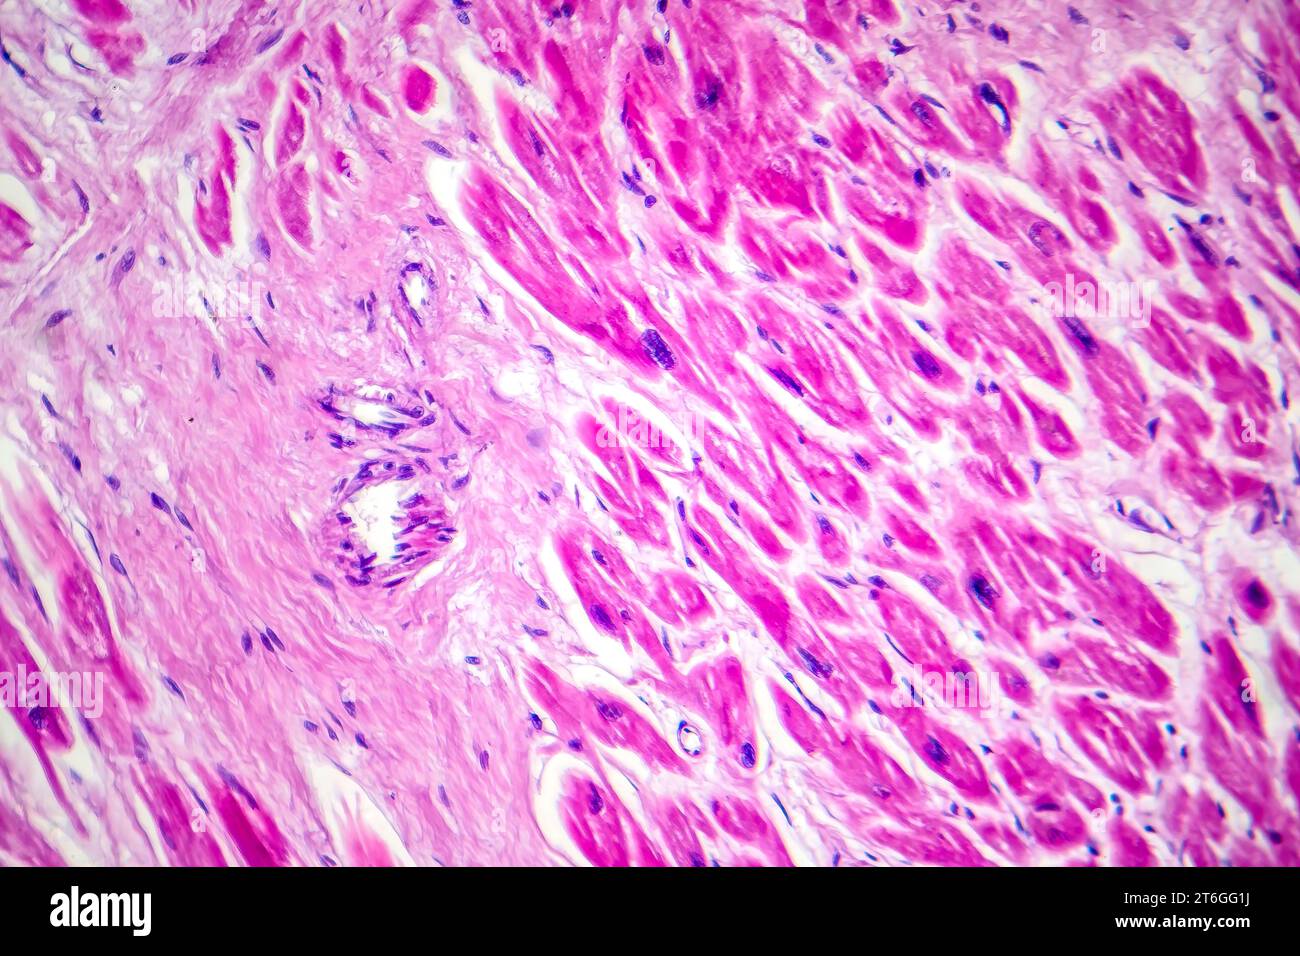

RF2T6GG1J–Photomikrographie des Myokardinfarkts, Darstellung von beschädigtem Herzgewebe durch verminderte Blutversorgung und Zelltod.